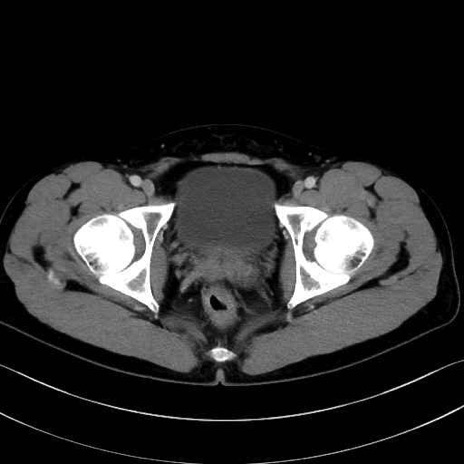

外閉鎖筋(obturator externus) のCT画像の解剖

外閉鎖筋 (Obturator externus)